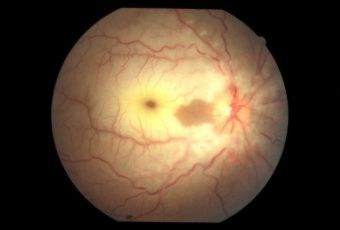

CENTRAL RETINAL VEIN OCCLUSION (CRVO) |

Confluent hemorrhages are the most prominent ophthalmoscopic feature of an acute ischemic central retinal vein occlusion These hemorrhages occur in a wide variety of shapes and sizes; they are usually concentrated in the posterior pole, but may be seen throughout the retina. Many hemorrhages are flame shaped, reflecting the orientation of the nerve fibers. Dot and punctate hemorrhages are interspersed and indicate involvement of the deeper retinal layers. Bleeding may be extensive, erupting through the internal limiting membrane to form a preretinal hemorrhage or extending into the vitreous. Small dot hemorrhages may be seen either isolated or clustered around small venules. The entire venous tree is tortuous, engorged, dilated, and dark. The retina is edematous, particularly in the posterior pole; some of this edema may obscure portions of the retinal vessels. Cotton-wool patches (soft exudates) are often present. The disc margin is blurred or obscured, and the precapillary arterioles appear engorged. Splinter hemorrhages and edema are present on the disc surface and extend into the surrounding retina. The physiologic cup is filled, and the venous pulse is absent. The arterioles, often overlooked because of the other more striking pathologic features, are frequently narrowed. Sometimes in central retinal vein occlusion of acute onset, the fundus picture is less dramatic, and all of the findings previously discussed may be present, but to a lesser degree. Vision depends on extent of macular involvement